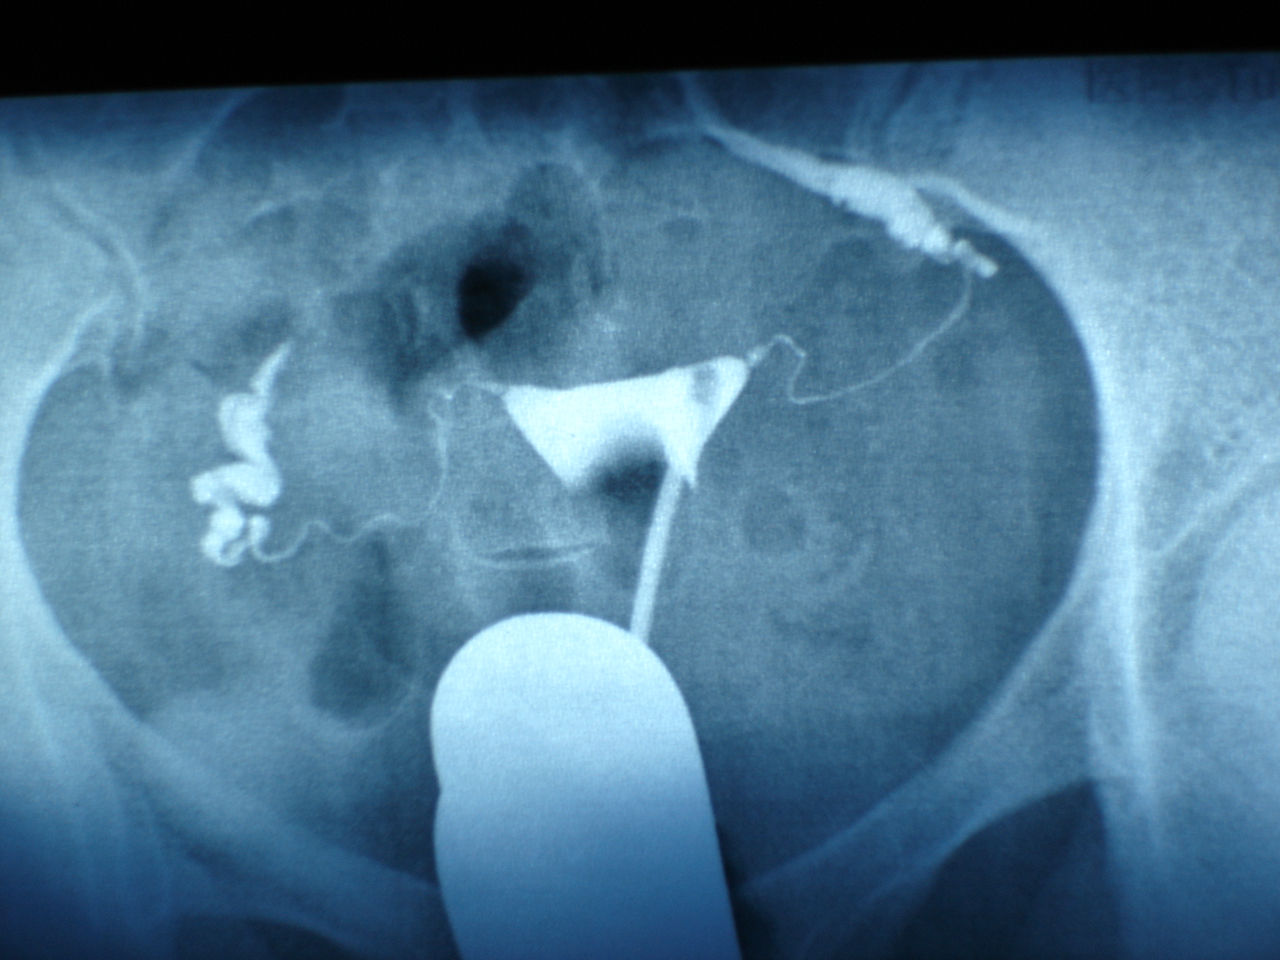

她輸卵管阻塞,做了3次試管嬰兒都失敗,轉到博元婦產科,先以腹腔鏡手術,再做試管嬰兒,竟3胞胎 不孕症: 雙邊輸卵管阻塞 ...